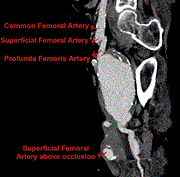

Successful treatment of a large profunda femoris artery aneurysm and associated pseudoaneurysm using endovascular stenting

Rebecca Jess and others

Journal of Surgical Case Reports, Volume 2024, Issue 4, April 2024, rjae221, https://doi.org/10.1093/jscr/rjae221